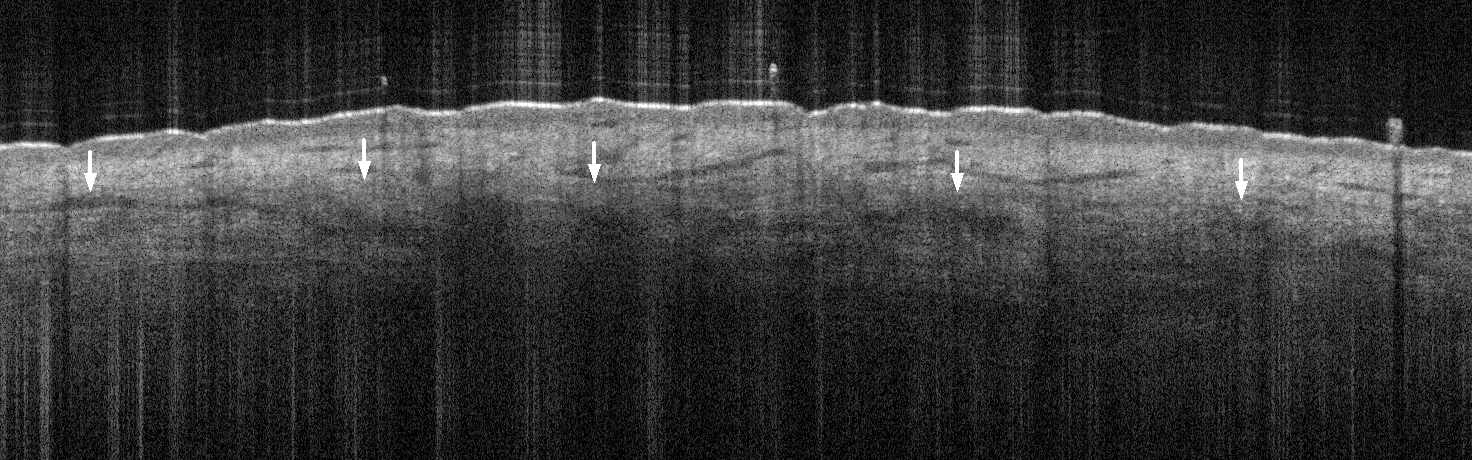

Reticular Dermis Lowest visible layer of follicular skin Hyporeflective mottled texture due to hyperreflective collagen bundles and a high fluid content from tissue fluid perfusion and vessels Leave a comment Cancel reply You must be logged in to post a comment.